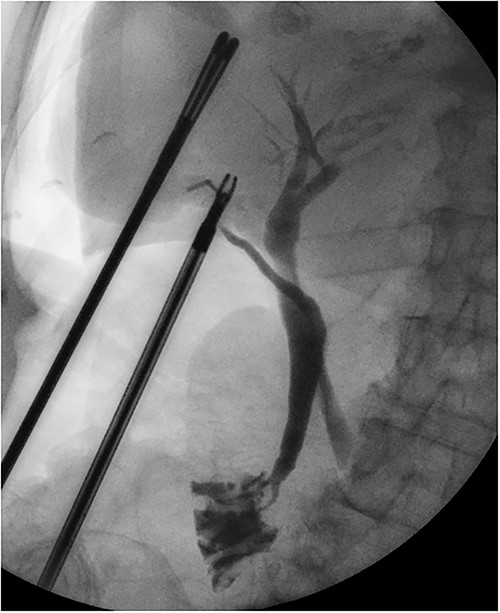

She had a good functional baseline, living in home independently and following anaesthetic review; after a family discussion, the consensus was to proceed to surgery. She underwent a laparoscopic cholecystectomy, and intraoperatively, the diagnosis of gallbladder volvulus was confirmed. A distended gangrenous gallbladder was found, which had undergone 360° clockwise rotation about the cystic duct (Figs 2, 3). The gallbladder was detorted to facilitate a traditional dissection of Calot’s triangle, achieving the critical view of safety (Figs 4, 5). The cystic duct was able to be cannulated facilitating an intraoperative cholangiogram which was unremarkable (Fig. 6). The gallbladder was then removed, and operation was completed without any complications. The histopathology of the gallbladder found diffuse haemorrhagic necrosis of the gallbladder without any evidence of dysplasia or malignancy. No cholelithiasis was present.

Intraoperative cholangiogram showing a long tortuous cystic duct with a medial insertion into the common bile duct.